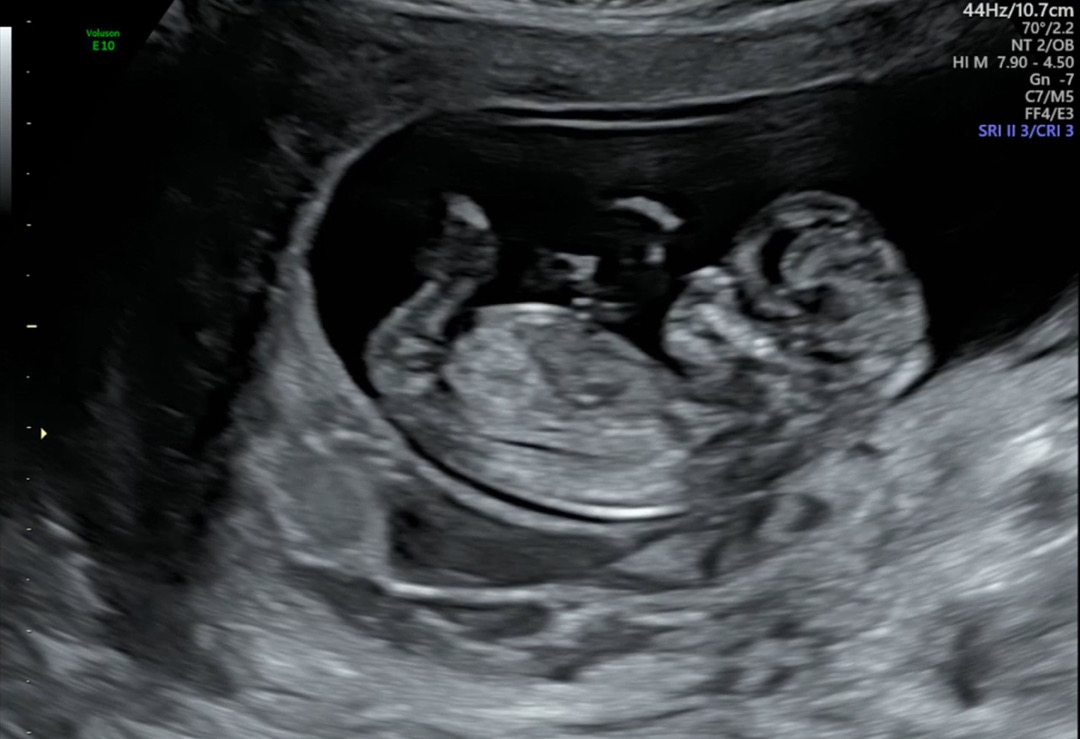

오늘 니프티 결과 나왔어요~

초음파상 문제 없었지만 마음 편하고자 니프티 했는데, 기다리면서 넘 떨렸네요! 태몽도 과일 하나, 큰 구렁이 하나여서 아들인가 딸인가 헷갈렸는데, 우리 말랑이는 딸이래요💜 성별이 뭐든 좋았겠지만 바라던 딸맘이 되어 더 좋네요🥰